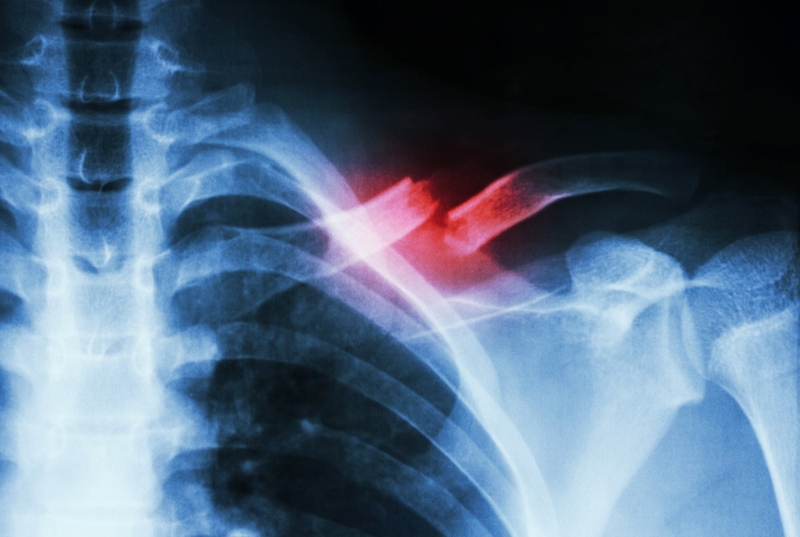

Chỉ định X-quang của bác sĩ là chụp bả vai thẳng, nghiêng. Các hình ảnh trên X-quang sẽ cho thấy xương có dấu hiệu bị tiêu hủy: Nang xương hoặc mất Calcium xương. Đồng thời cũng cho thấy hình ảnh khối u có bờ mỏng, nham nhở hoặc không có bờ.